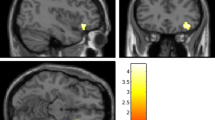

We investigated the relationship between rWMD and individual differences on the UCLA Loneliness Scale. A multiple regression analysis of age, gender, general intelligence and total intracranial volume (TIV: total GM volume + total WM volume + total cerebrospinal fluid volume) revealed that the loneliness score was significantly negatively correlated with rWMD in the bilateral IPL, left pSTS, left posterior TPJ, right AI, left mPFC and left rostrolateral prefrontal cortex (RLPFC) at P < 0.05 (false discovery rate [FDR] corrected) (Fig. 2 and Table 3). We found no significant positive correlations between rWMD and UCLA Loneliness Scale score at P < 0.05 (FDR corrected).

Regions showing a correlation between rWMD and UCLA Loneliness Scale scores.

The red-to-yellow colour scale indicates the t-score for the negative correlation between rWMD and UCLA Loneliness Scale score (P < 0.0025, uncorrected and k > 100 for visualisation purposes). Regions showing correlations were overlaid on preprocessed, smoothed-mean rWMD images using templates created from 63 subjects who participated in a previous experiment in our laboratory. The left inferior parietal lobule (IPL, x, y, z = −41, −46, 36) showed areas of significant correlation in the bilateral inferior parietal lobule (IPL) and left posterior temporoparietal junction (pTPJ) (a1). A scatterplot of UCLA Loneliness Scale scores and mean rWMD values in the significant clusters in the left IPL (a2). Dorsomedial prefrontal cortex (dmPFC, x, y, z = −17, 60, 10) showing regions of significant correlation in the left posterior superior temporal sulcus (pSTS), right anterior insula (AI), left dmPFC and left rostrolateral prefrontal cortex (RLPFC) (b1). A scatterplot of the UCLA Loneliness Scale scores and mean rWMD values in the significant clusters in the left dmPFC (b2).